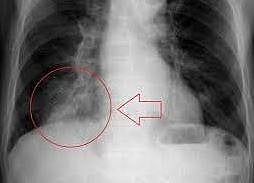

पिंपरी : पिंपरीच्या डीपीयू सुपर स्पेशालिटी हॉस्पिटलच्या डॉक्टरांना 85 वर्षीय रुग्णाच्या फुप्फुसामध्ये अडकलेला हळकुंडाचा तुकडा काढण्यात यश आले आहे. शेतकरी असलेल्या 85 वर्षीय व्यक्तीला तीन महिन्यांपासून सतत खोकला सुरू होता. पिंपरीच्या डीपीयू सुपर स्पेशालिटी हॉस्पिटलमध्ये आल्यावर डॉक्टरांनी फुप्फुसाचा सीटी स्कॅन करण्याचा सल्ला दिला आणि त्यामध्ये त्यांना रुग्णाच्या फुप्फुसात बाहेरील वस्तू अडकली असल्याचे आढळून आले. श्वसन विकार विभागाचे प्रमुख डॉ. एम. एस. बरथवाल यांच्या नेतृत्त्वाखाली त्यांच्या टीमच्या डॉक्टरांच्या पथकाने रुग्णाची ब्रॉन्कोस्कोपी केली.

फुप्फुसांमध्ये अडकलेल्या वस्तूभोवती पिवळ्या रंगाचे थर तयार झाले होते, ते काढणे कठीण झाले. चिमटा आणि विशेष साधनांचा वापर करून, वैद्यकीय पथकाने अत्यंत गुंतागुंतीच्या प्रयत्नानंतर व इजा न करता फुप्फुसामध्ये अडकलेली वस्तू काढली. ती वस्तू कोणती असेल हे समजण्यास डॉक्टरांना सुरुवातीला वेळ लागला. मात्र, ती वस्तू कापल्यानंतर, त्यांना त्याचा रंग पिवळसर असल्याचे आढळले. रुग्णाशी प्रक्रियेनंतरच्या संवादादरम्यान, त्याने खोकला कमी करण्यासाठी झोपण्यापूर्वी तोंडात हळकुंडाचा तुकडा ठेवल्याचे सांगितले. त्यावेळी डॉक्टरांनी असा निष्कर्ष काढला की हळकुंडाचा तुकडा झोपेच्या वेळी चुकून फुप्फुसात शिरला असावा आणि अनावधानाने त्याच्या श्वसननलिकेत गेला असावा. पूर्णपणे बरे झाल्यावर रुग्णाला घरी सोडण्यात आले.